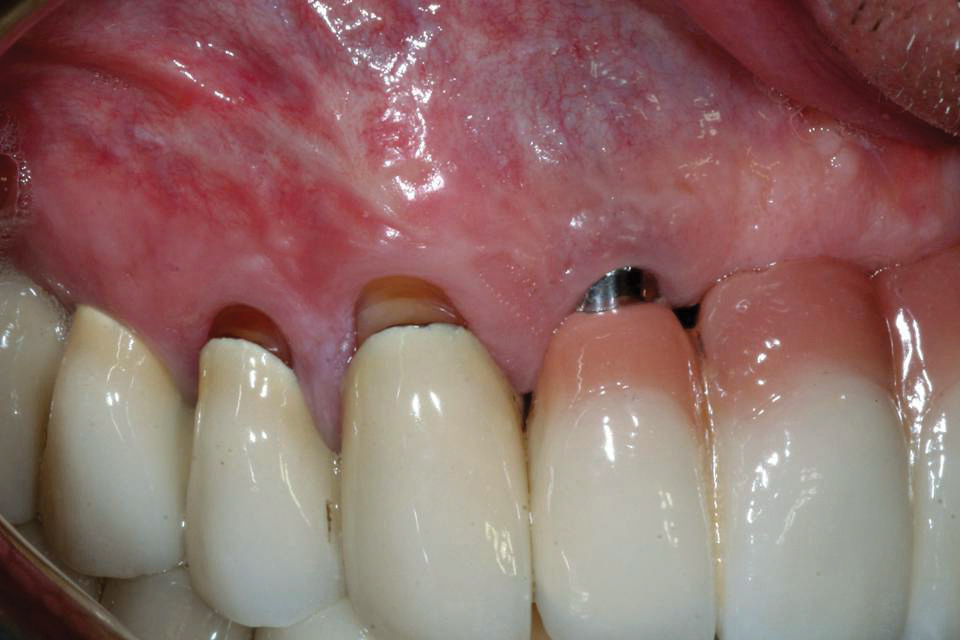

Modified Tunnel Technique and DoubleLayer Acellular Dermal Matrix to

Modified Tunnel Technique and DoubleLayer Acellular Dermal Matrix to Matrix Graft Dental Suggested that success with the acellular dermal matrix graft is highly. Since its introduction to dentistry in 1999, alloderm select™ regenerative tissue matrix (rtm) has been a widely accepted acellular. The aim of this systematic review was to evaluate whether patients with gingival. Acellular dermal matrix (adm) has been used for more than two decades as a connective graft substitute. Matrix Graft Dental.